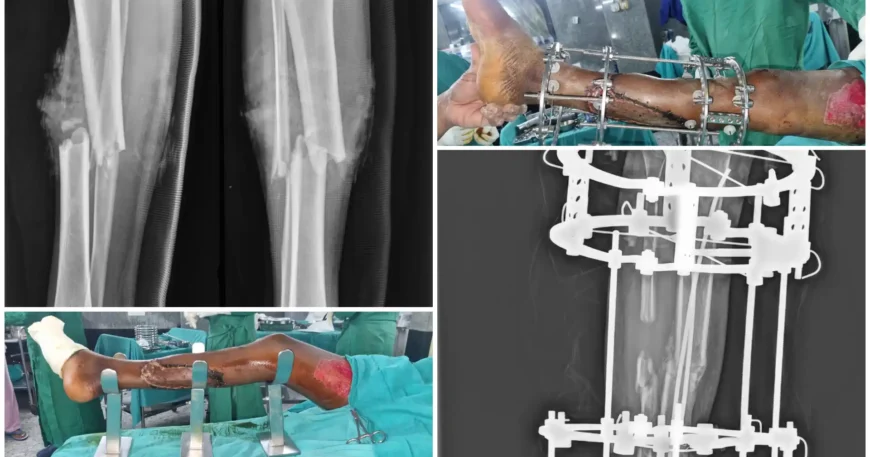

Compound Right Tibia Fracture with Type 3B Wound Treated with TENS Nailing, Ilizarov Fixation & Bone Grafting | Balanku Hospital

Severe open fractures of the tibia are among the most challenging orthopedic injuries. When associated with extensive soft tissue damage, such as a Type 3B wound, treatment requires staged surgical management, infection control, and advanced limb reconstruction techniques.

At Balanku Hospital, we specialize in complex trauma care and limb salvage procedures. We are pleased to share the successful recovery of Mr. Anjinayya, who presented with a compound fracture of the right tibia with a Type 3B open wound.

Clinical examination and imaging confirmed a compound (open) fracture of the right tibia with a Type 3B wound, indicating significant bone fracture along with extensive soft tissue injury requiring surgical reconstruction.

The first step involved stabilization of the fracture using TENS (Titanium Elastic Nailing System) to maintain alignment and support bone healing.

Simultaneously, proper wound debridement was performed to remove contaminated and non-viable tissue.

Due to the extensive soft tissue defect, skin grafting was performed to cover the exposed area and promote proper wound healing.

To enhance stability and promote bone healing, Mr. Anjinayya later underwent Ilizarov fixation, an advanced external ring fixation technique used in complex fractures and bone defects.

To stimulate bone union and address any bone loss, bone grafting was performed. This procedure enhances biological healing and strengthens the fracture site.

After achieving adequate bone healing and stability, the Ilizarov fixator was removed.

With staged surgical management, infection control, and structured rehabilitation, Mr. Anjinayya achieved: